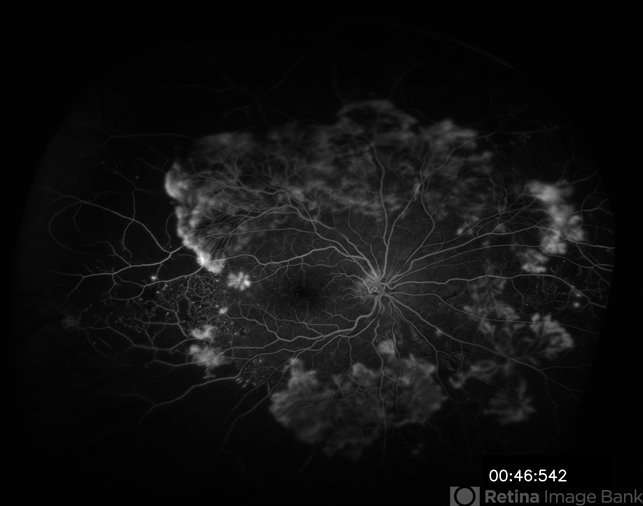

- sea fan, fibrovascular proliferation, proliferative diabetic retinopathy (PDR)

- Eitae Kim, BOIM retinal center, Pureun eye hospital

- Scanning laser ophthalmoscope

- UWF FAG image of 55-year-old male with PDR before treatment.